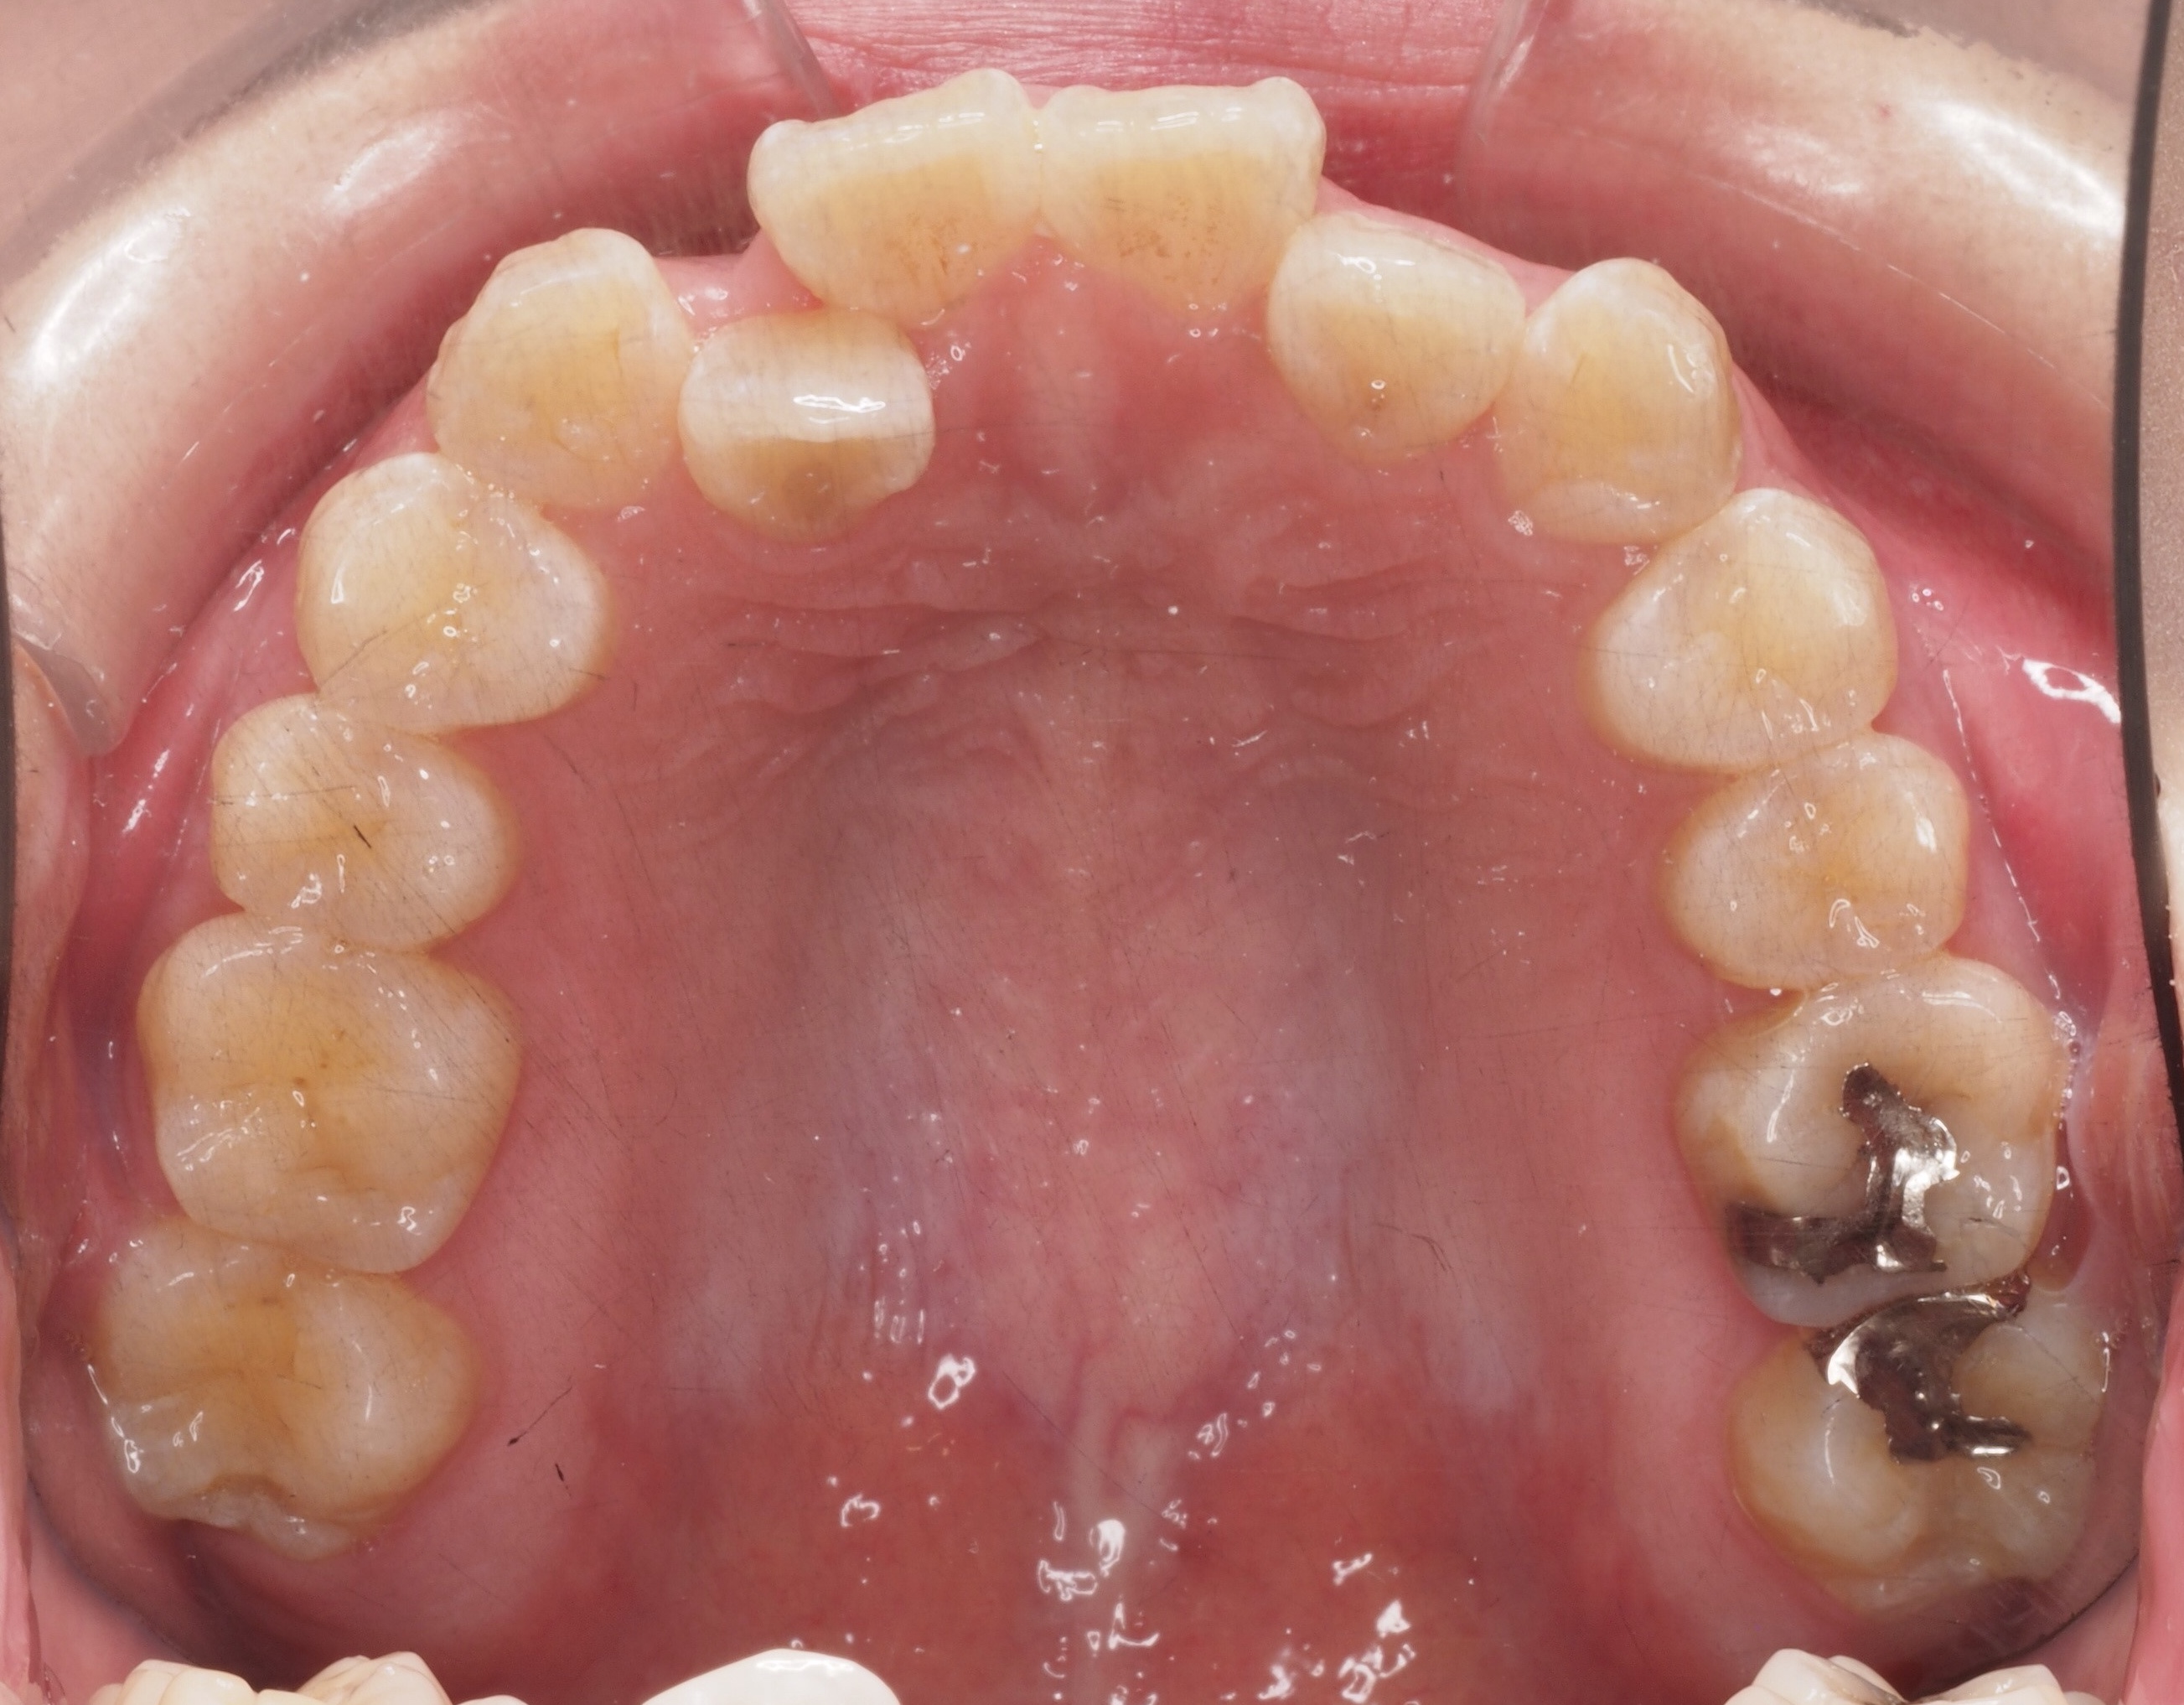

矯正スタート時(上顎)撮影:2018.07↓ 矯正9ヶ月経過(上顎)撮影:2019.04↓

上顎はまだまだ時間がかかりそうです…😢

前歯の隣の歯(2番)は左右どちらも少しですが前に出てきた気がします!